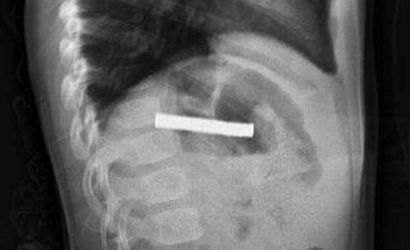

Elazığ'da 3 yaşındaki bir çocuk, oyun oynadığı sırada bulduğu 19 mıknatısı yuttuktan sonra rahatsızlanarak hastaneye kaldırıldı. Bu durum, Fırat Üniversitesi Hastanesi'nde gerçekleştirilen başarılı bir operasyonla son buldu.

Fırat Üniversitesi Çocuk Gastroenteroloji Hepatoloji ve Beslenme Bilim Dalı Başkanı Prof. Dr. Yaşar Doğan, burada yaptığı muayenelerde mıknatısların çocuğun yemek borusunu tıktığını belirledi. Doğan ve ekibi, çocuğun yemek borusundaki mıknatısları çıkarırken, işlem sırasında bazı hasarların oluştuğunu ancak iyi bir müdahale ile durumun kontrol altına alındığını ifade etti. "Mıknatıslar, hastanın midesine alındı ve oradan özel bir file ile çıkarıldı. İşlemden sonra çocuğu gözlem altında tuttuk ve sabah aile kendi isteğiyle taburcu olmak istedi," dedi.

Elazığ'da 3 yaşındaki çocuğun yuttuğu ve yemek borusunu tıkayan 19 mıknatıs, Fırat Üniversitesi Hastanesi'nde yapılan başarılı bir operasyonla çıkarıldı.